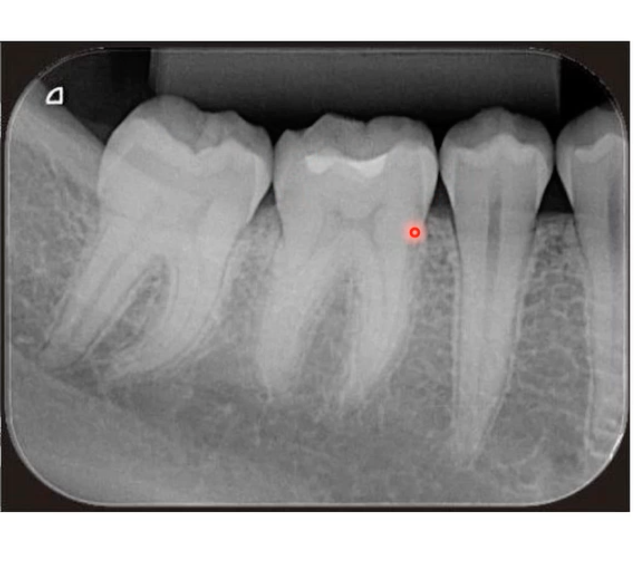

Periapical -lets you see crowns and roots

Bitewing- lots of crowns of both arches at the same time

Right bitewing will have the molars on LHS and premolars on RHS

Left bitewing has molars on RHS and premolars LHS

Its like looking at patient head on, their molars are further back in their head(towards outside of image)